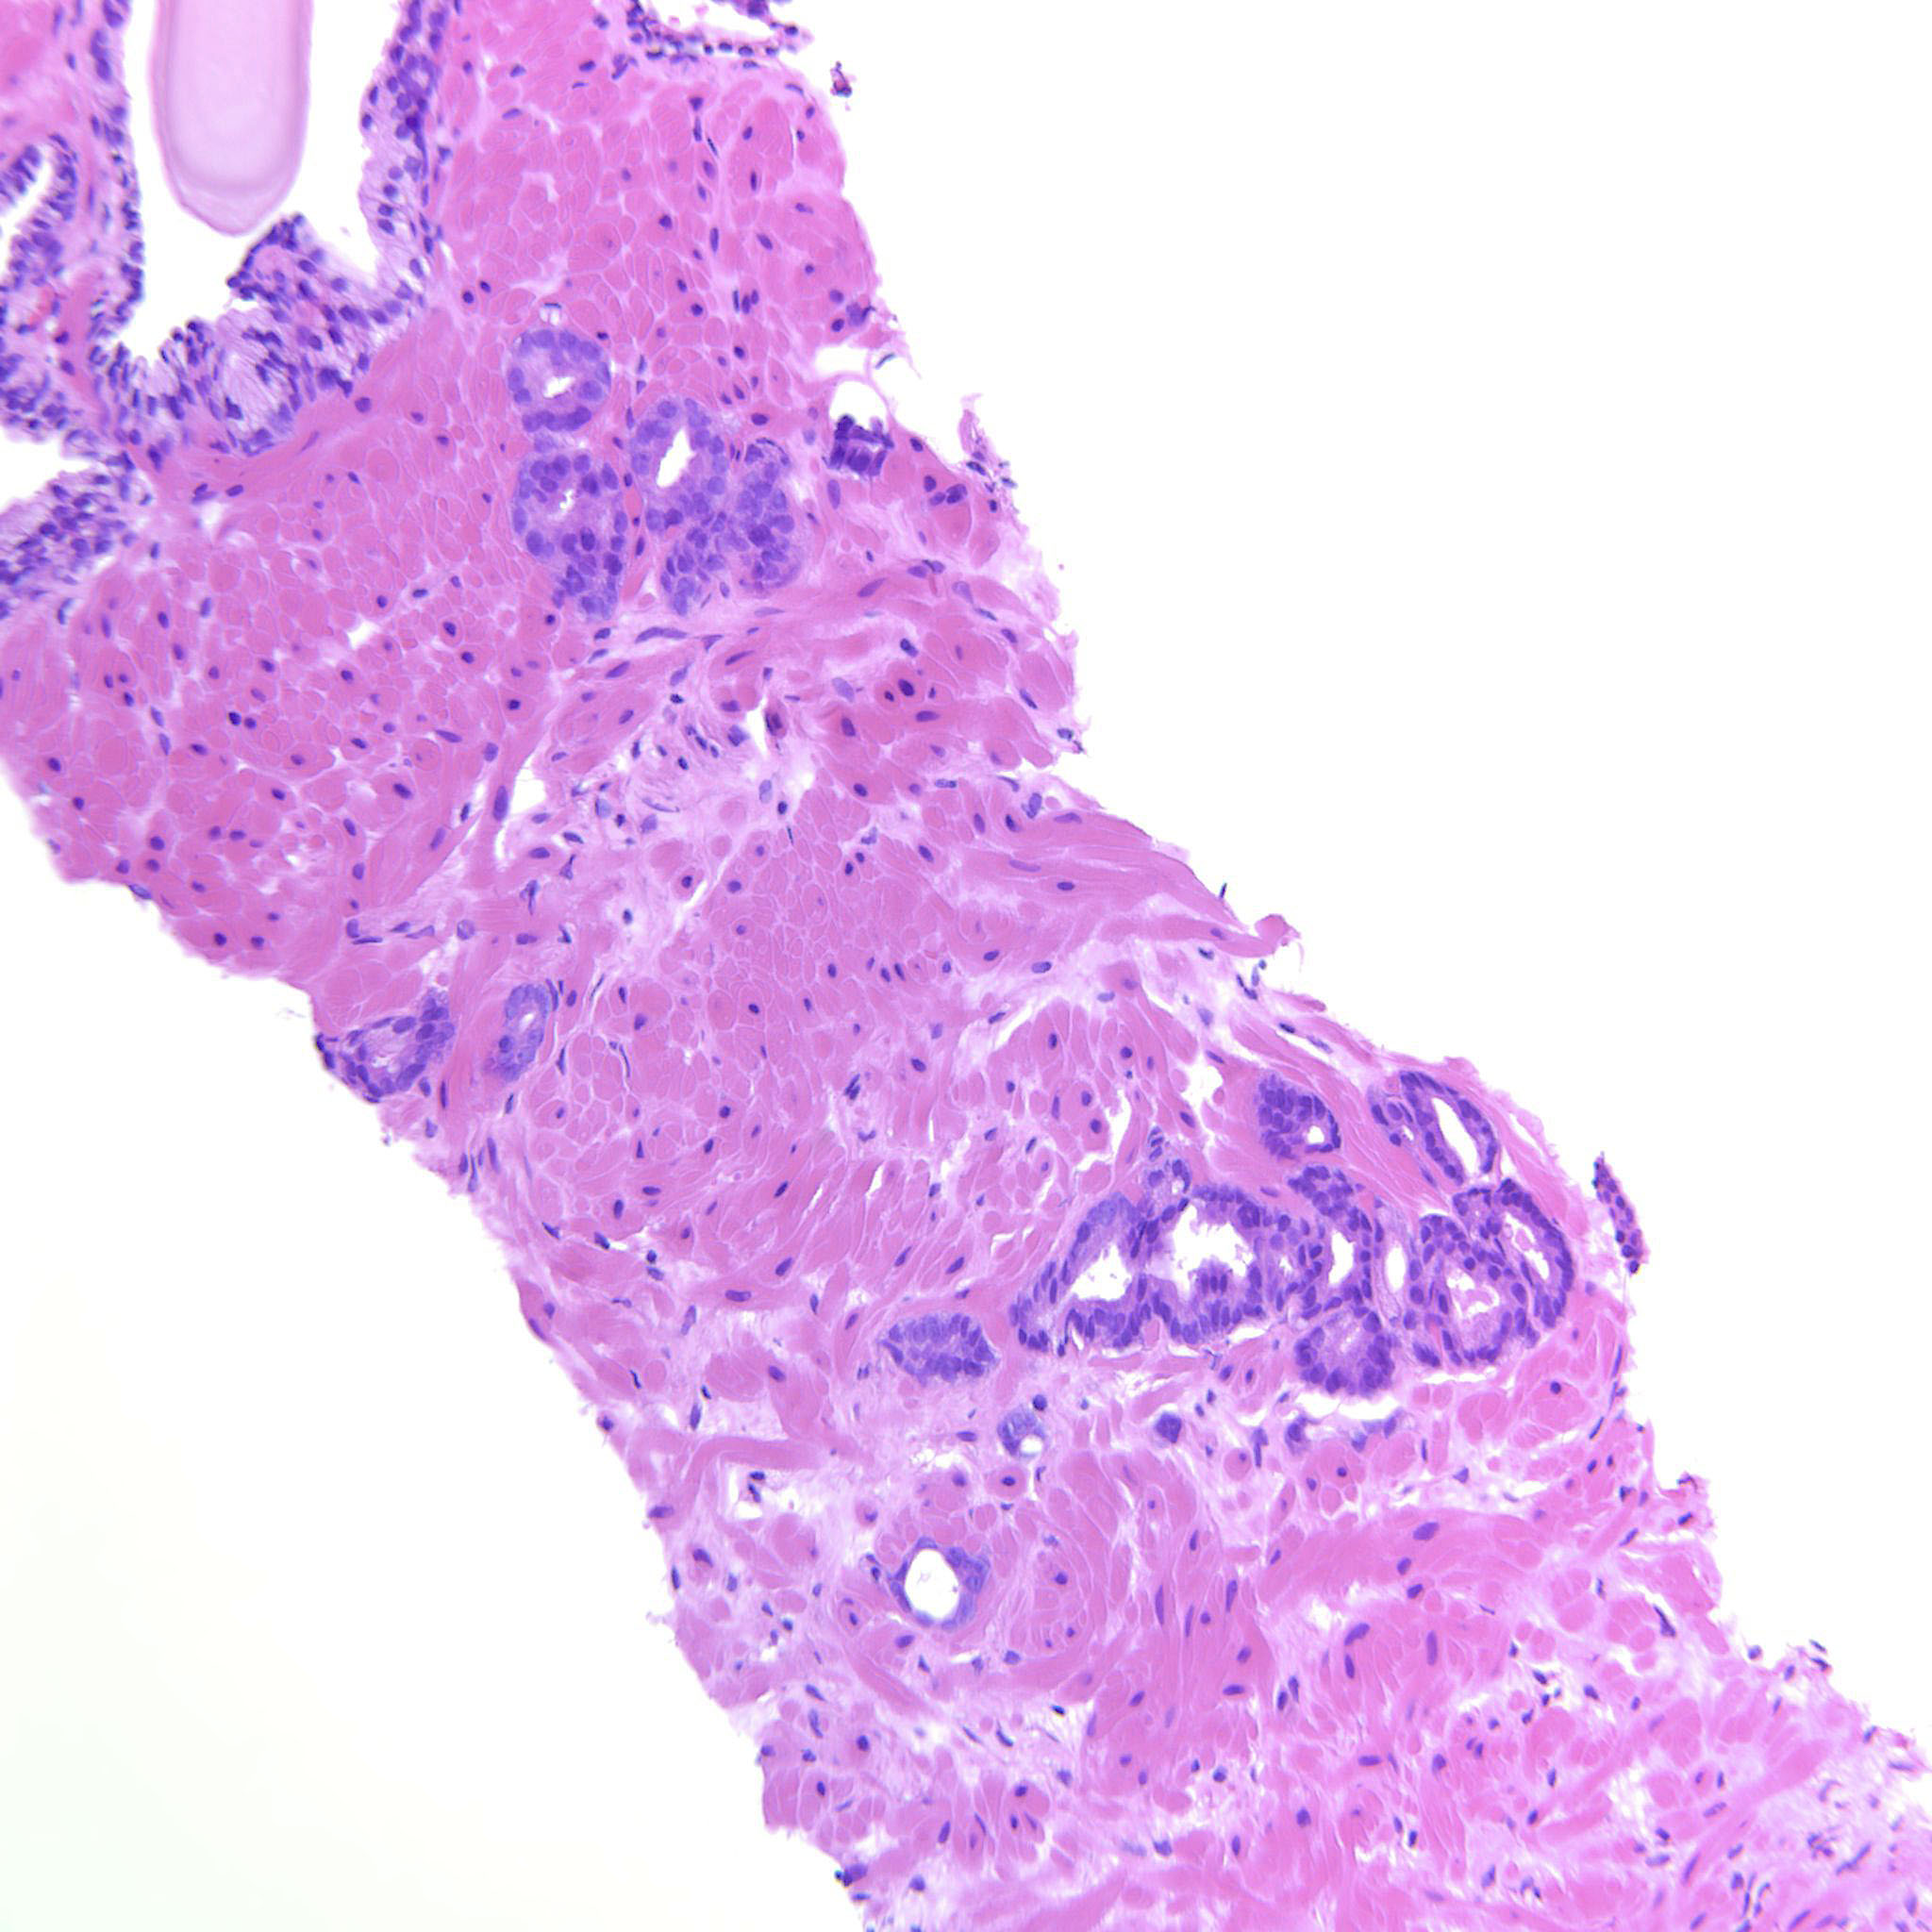

Consensus grade: GS 3+3=6 (ISUP 1)

Case description (by case creator):

A couple of groups of well-formed glands with a few structures that most likely are tangential cuts.